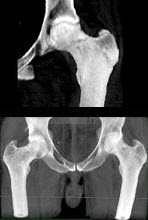

32、单项选择题

女,69岁,摔伤后左髋部疼痛,活动受限8小时,结合影像学检查,最可能的诊断是()

A.股骨头骨折

B.肱骨骨折

C.蒙泰贾骨折

D.骨盆骨折

E.股骨颈骨折

点击查看答案